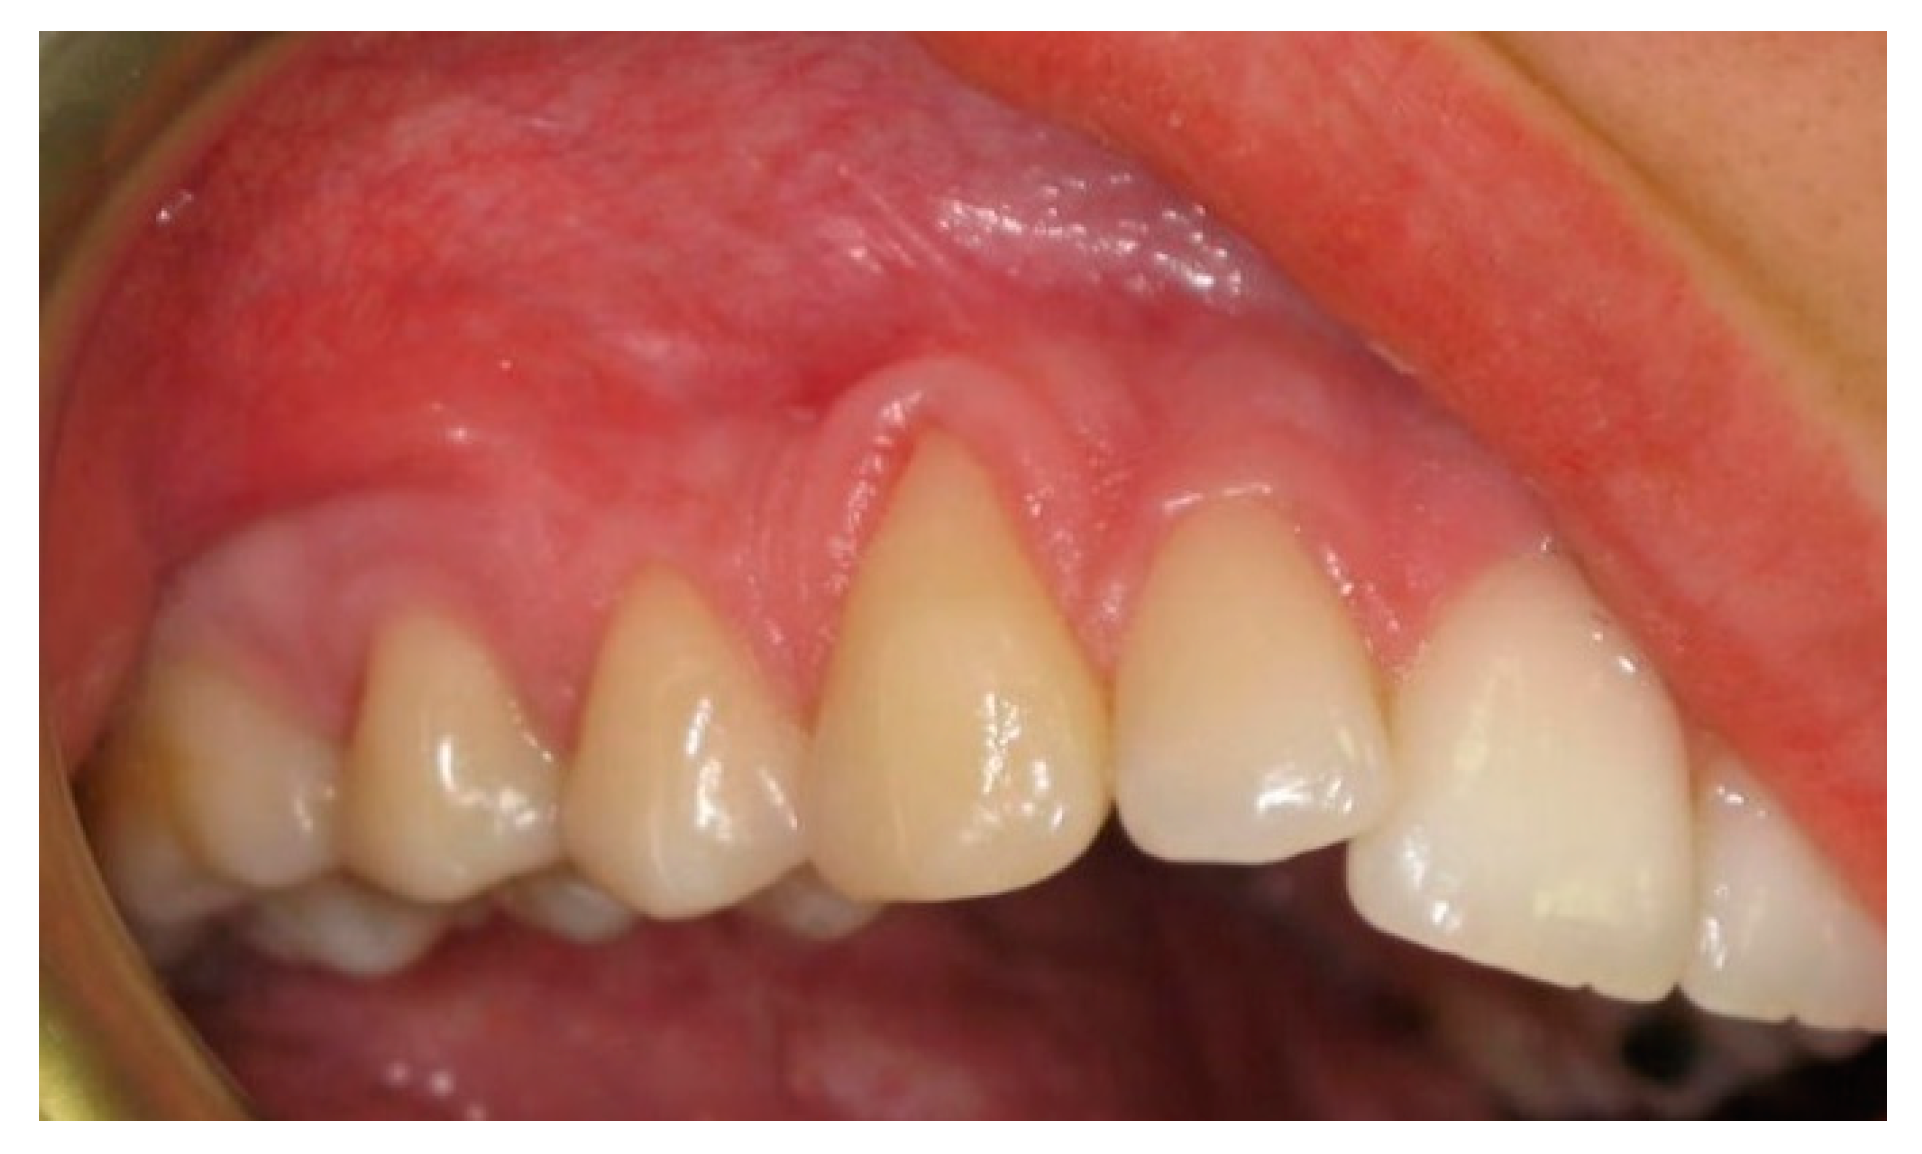

:1. Introduction

2. Materials and Methods

2.3. Surgical Procedures